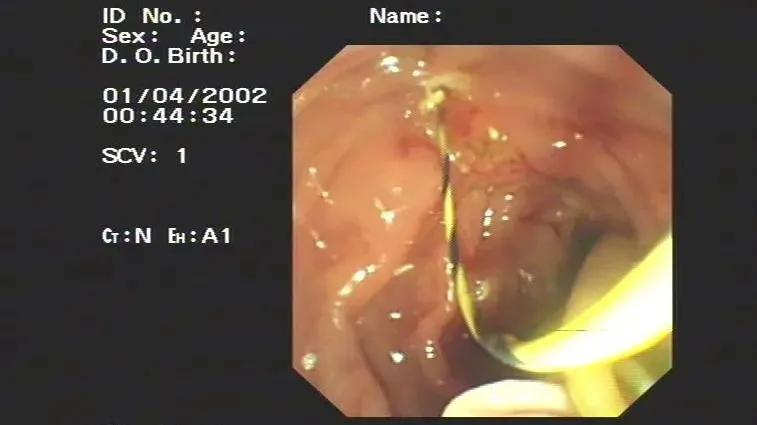

接诊的医生首先考虑到了存在胆道蛔虫的情况,但儿童家属表示没有发现过有类似情况,经过完善磁共振检查,发现胆管的下段存在一团可疑的条索团块,经过保守治疗,患儿每天都有数次剧烈的腹痛,家长经过慎重考虑,同意了肝胆外科医师的进行内镜ERCP治疗的意见。

经过1个小时左右的内镜手术操作,从胆总管内拖出了一团软绵绵的死亡虫体,而这就是引起腹痛的罪魁祸首。